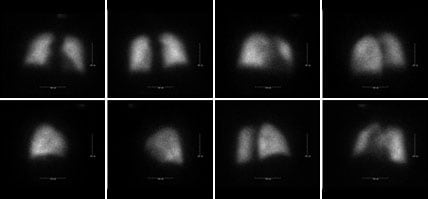

V/Q scan

A V/Q (ventilation/perfusion) scan is recommended and is the preferred method by experts in the field to screen for CTEPH. It can reveal areas in the lung that are not receiving blood as expected when you breathe.

Two tests make up a V/Q scan—a ventilation scan and a perfusion scan. During the ventilation scan, you inhale radioactive gas through a mask while lying under a scanner. The mask can cause some people to feel claustrophobic or nervous about being in a small space.

During the perfusion scan, your doctor injects a special solution into your vein and places you on a movable table under a scanner. The scanner allows your doctor to see how well blood is flowing through your lungs.

Negative

If your V/Q scan comes back negative, there is very little chance that you have CTEPH.

Image: Courtesy of G Heresi-Davila, Cleveland Clinic PTE Program.

Positive

If your V/Q scan comes back positive, you could have CTEPH. Your doctor will perform additional tests to confirm your diagnosis.

Image: Courtesy of the PTE Program at University of California, San Diego.